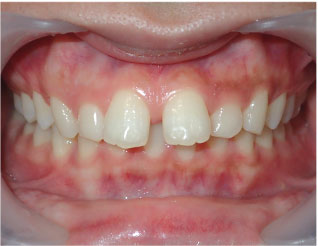

この方はクリアコレクトというマウスピース矯正で歯並び治療しました。 かなり外側に生えていた八重歯や引っ込んでいた下の前歯もきれいに整いました。 マウスピースは16枚、期間は8か月でした。